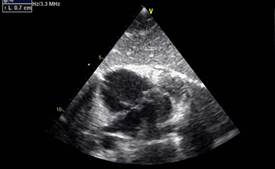

En subcostal 4 cámaras se observa CIA de 7 mm de diámetro con shunt de izquierda a derecha. (Figuras 2,3,4)

Video VIDEOS\CIA TT\CIA ETT.wmv, https://youtu.be/ihgC147F1-s